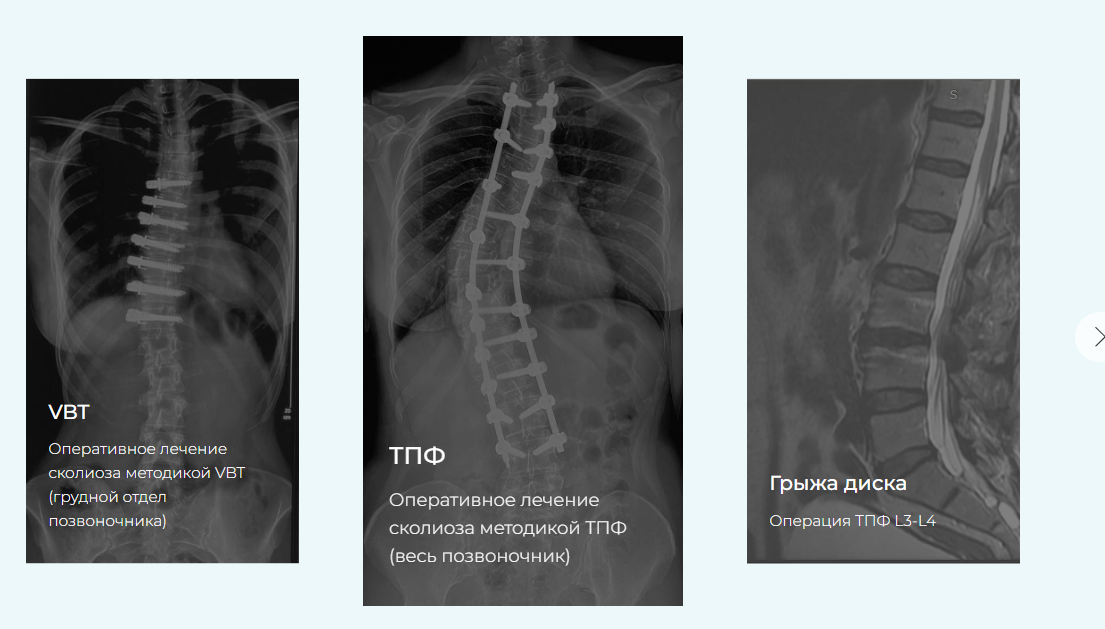

Этот курс разработан для восстановления пациентов спустя 3 месяца после операций по исправлению сколиотической деформации (методиками ASC, VBT и ТПФ), по исправлению кифотической деформации, удаления грыж межпозвонкового диска с фиксацией и без, фиксации после переломов позвоночника грудного и поясничного отделов, устранения спондилолистеза, а также для консервативного лечения остеохондроза и болей в спине.